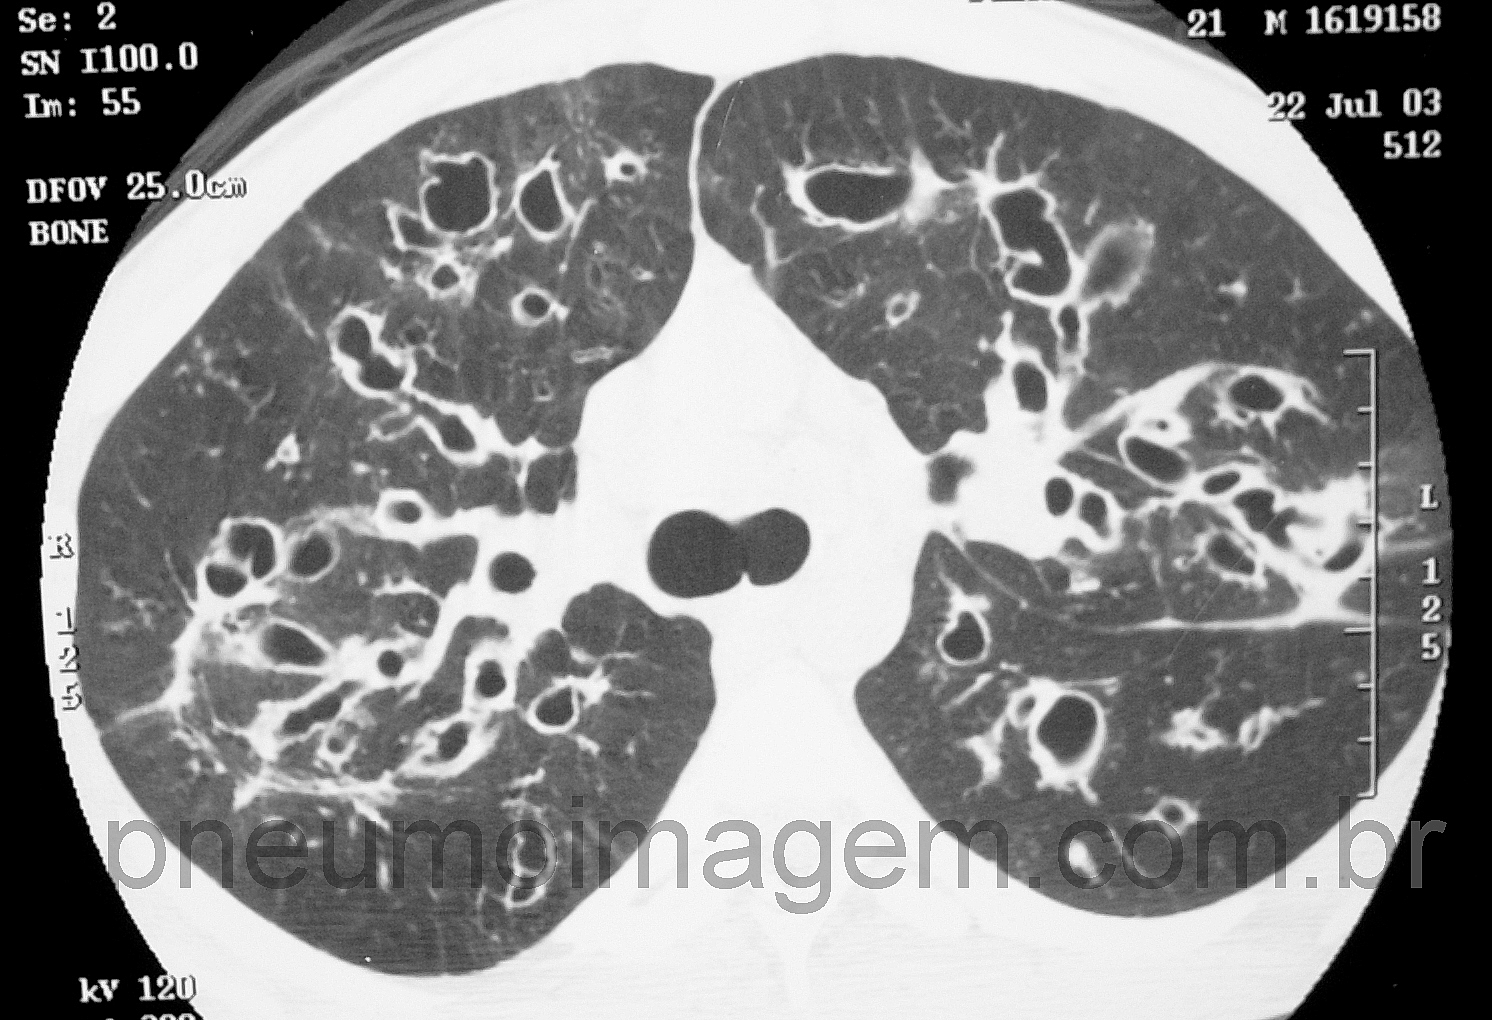

No final de outubro a tobramicina inalatória foi incorporada ao Sistema Único de Saúde (SUS) do Brasil. O aminoglicosídeo é usado para o tratamento da infecção crônica por Pseudomonas aeruginosa das vias aéreas em pacientes com fibrose cística. A medida foi tomada após consulta pública e discussão de especialistas da Comissão Nacional de Incorporação de Novas Tecnologias no SUS (Conitec).

O uso do medicamento leva a um ganho de 12% na função pulmonar aferida pelo VEF1, reduz a contagem de colônias de P. aeruginosa e diminui em 26% as internações (IC de 95%, 2-43%). O benefício da incorporação do medicamento também aparece na literatura com relação ao impacto econômico e é citado na publicação da Conitec. Uma análise realizada no Canadá observou redução de 43% nos dias de internação e de 44% nos gastos com antibioticoterapia. No Brasil, a comissão estimou que o impacto anual da incorporação do medicamento será de R$ 3.205.440,80.